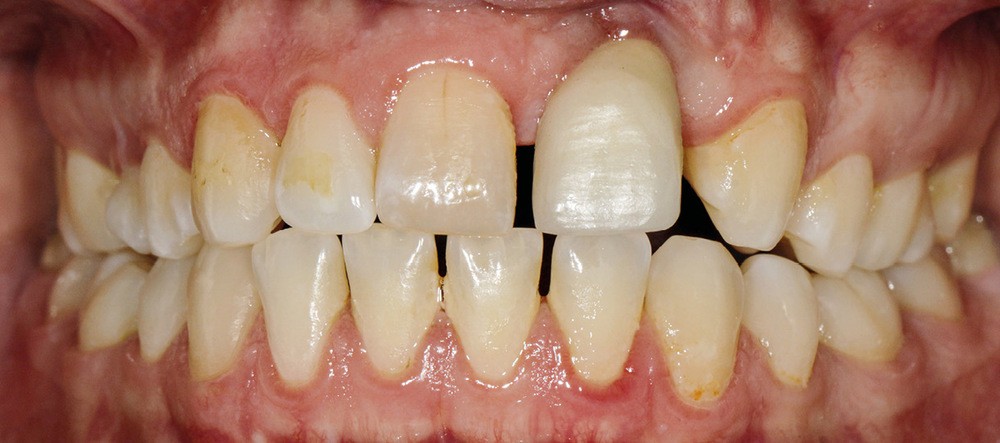

- au niveau esthétique : une couronne sur 21 disgracieuse et une déviation du milieu maxillaire vers la gauche (fig. 2) ;

- au niveau dentaire : une arcade maxillaire asymétrique avec déviation du milieu maxillaire à gauche. On note l’absence de 21, 22, 25, 35 et 45, une classe II droite et gauche avec infraclusion antérieure et la présence d’un implant en place de 21 avec un diastème de 3 mm entre 21 et 23 (fig. 3) ;